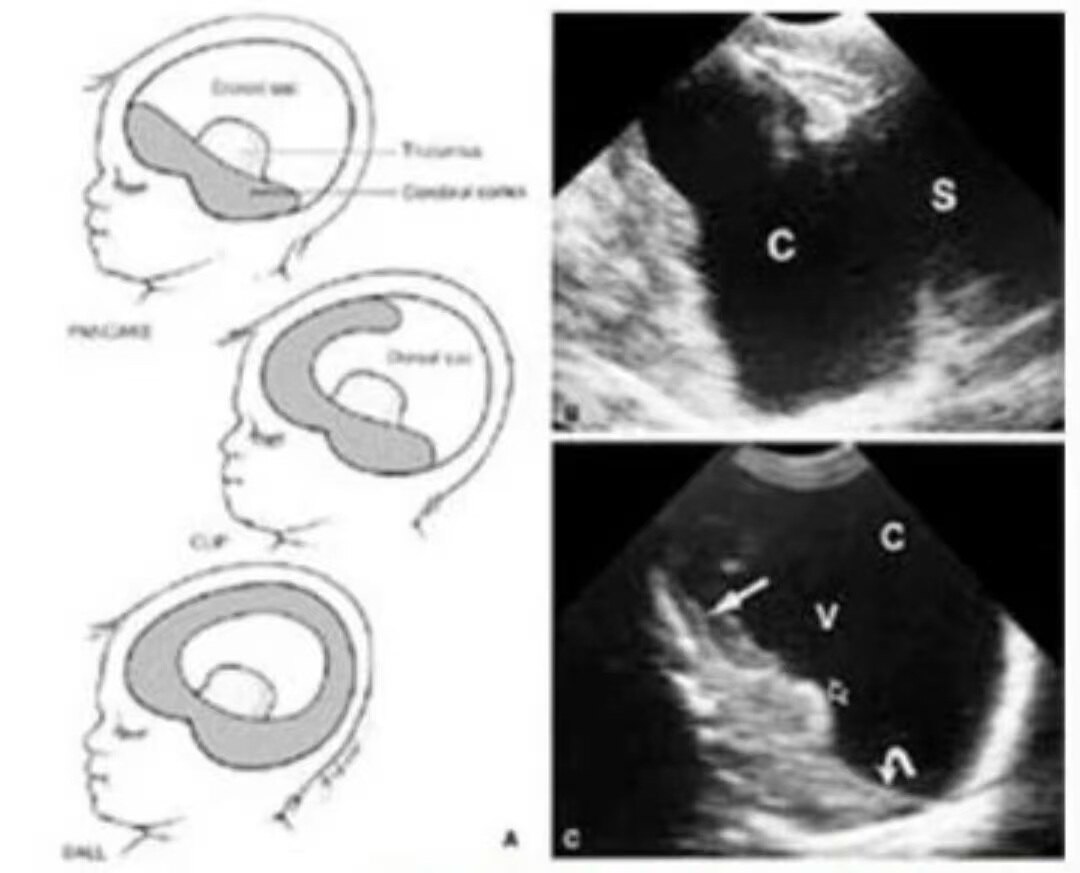

(A)矢状位显示残余脑组织和单一脑室。从上到下显示全前脑呈薄饼样,杯样和球样。灰色显示残余的脑组织。(B)新生儿矢状位,显示杯样无叶全前脑,C单一脑室,向后延伸为背囊S。

(C)矢状位显示薄饼样全前脑,V单一脑室腔向后延伸为背囊C。枕叶脑组织(弯箭)和额叶脑组织(直箭),以及脉络丛(开口箭)可见。